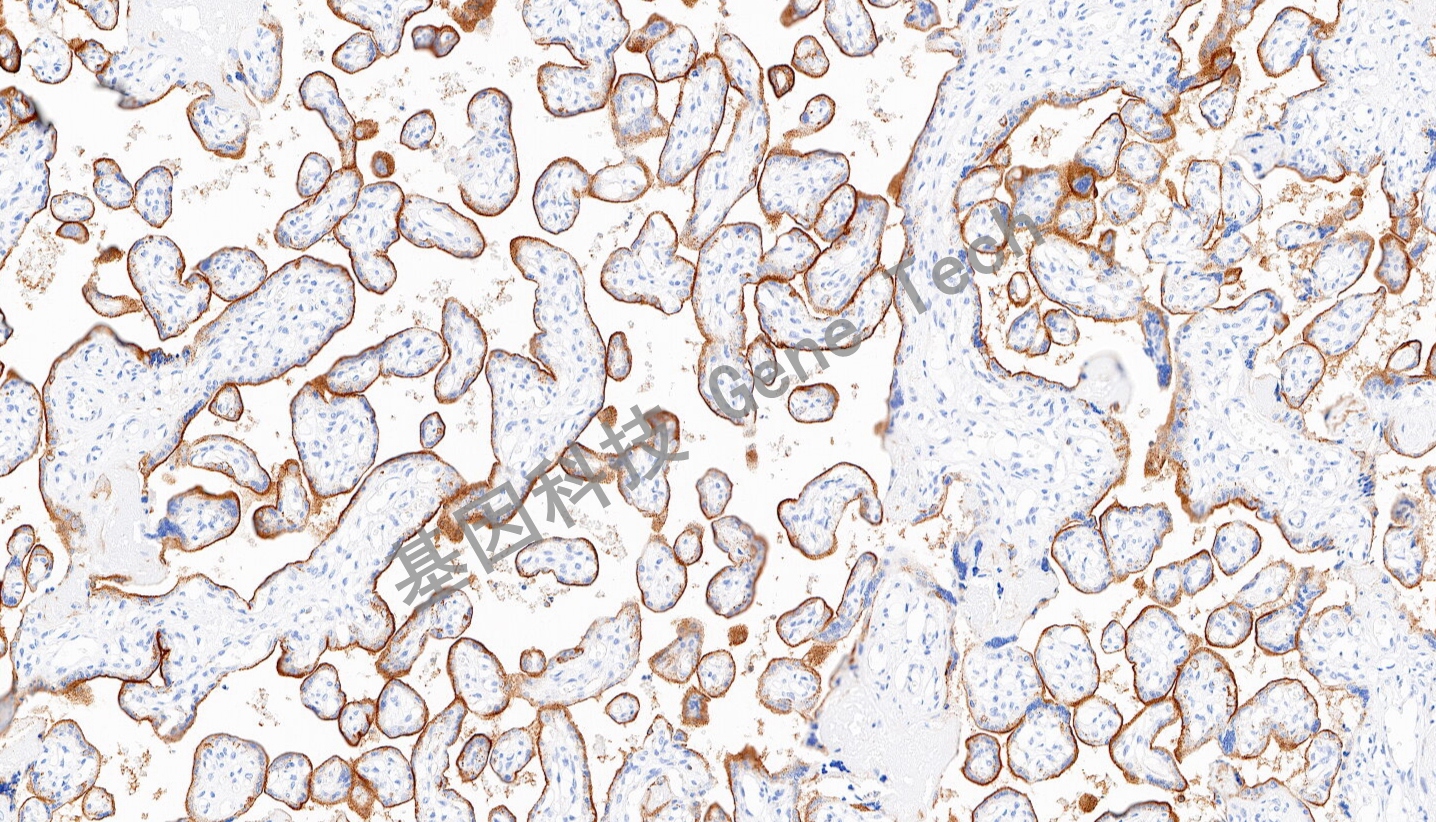

| 預(yù)處理:高pH熱修復(fù) | 陽性部位:細胞漿 | 陽性對照:胎盤 |

| 胎盤石蠟切片,用 VISTA(GT2461)染色,細胞漿陽性,DAB 顯色。 | ||